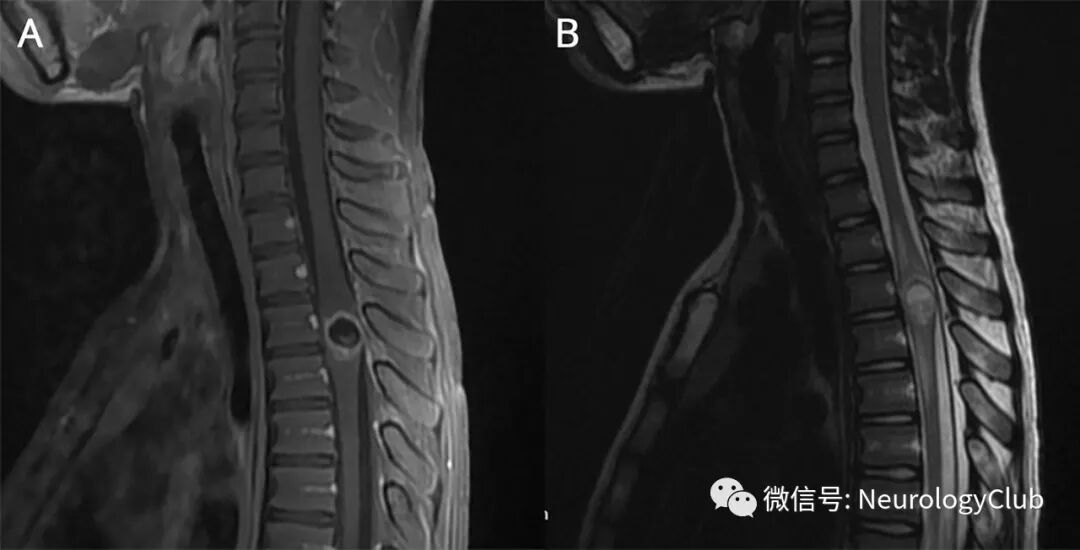

10岁男孩,因下肢肌力下降入院。查体提示孤立性痉挛性下肢轻瘫。胸椎MRI可见髓内囊性病变(图1)。

(图1:A:矢状位增强T1;B:矢状位T2WI;MRI可见位于T3-T4水平的髓内囊性病变,伴厚壁和强化,周边可见血管源性水肿;病变在T2WI上呈高信号[由于囊液的蛋白质成分],T1上WI可见条纹状高信号[或提示退化的头节],符合囊虫病胶体期[可貌似肿瘤性病变])